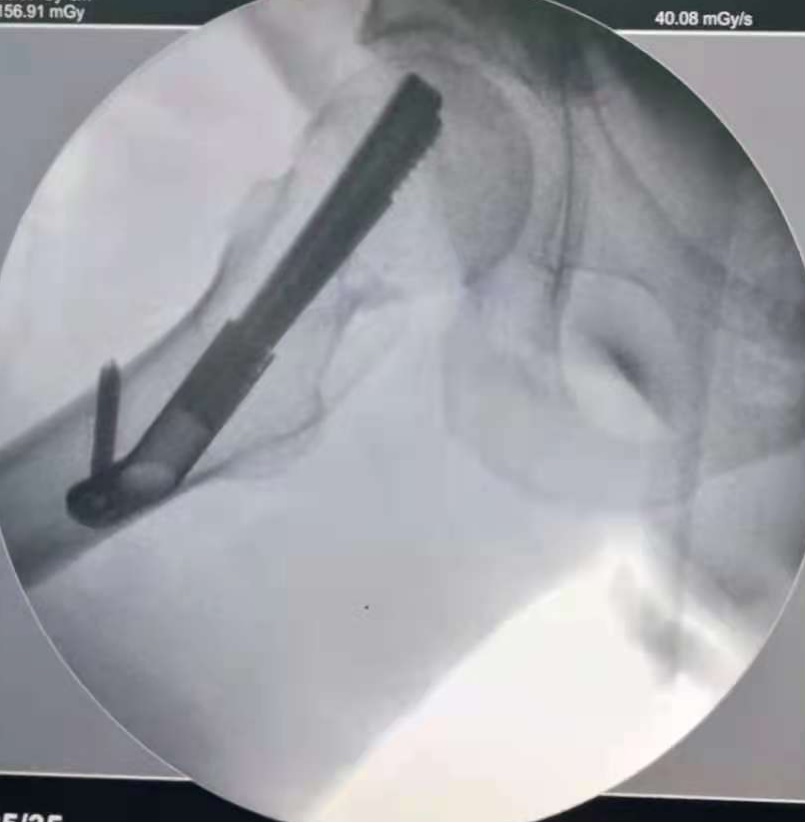

术后复查右髋部正位片和蛙式位片评估骨折复位情况,效果满意。

图4 透视见股骨颈骨折复位良好